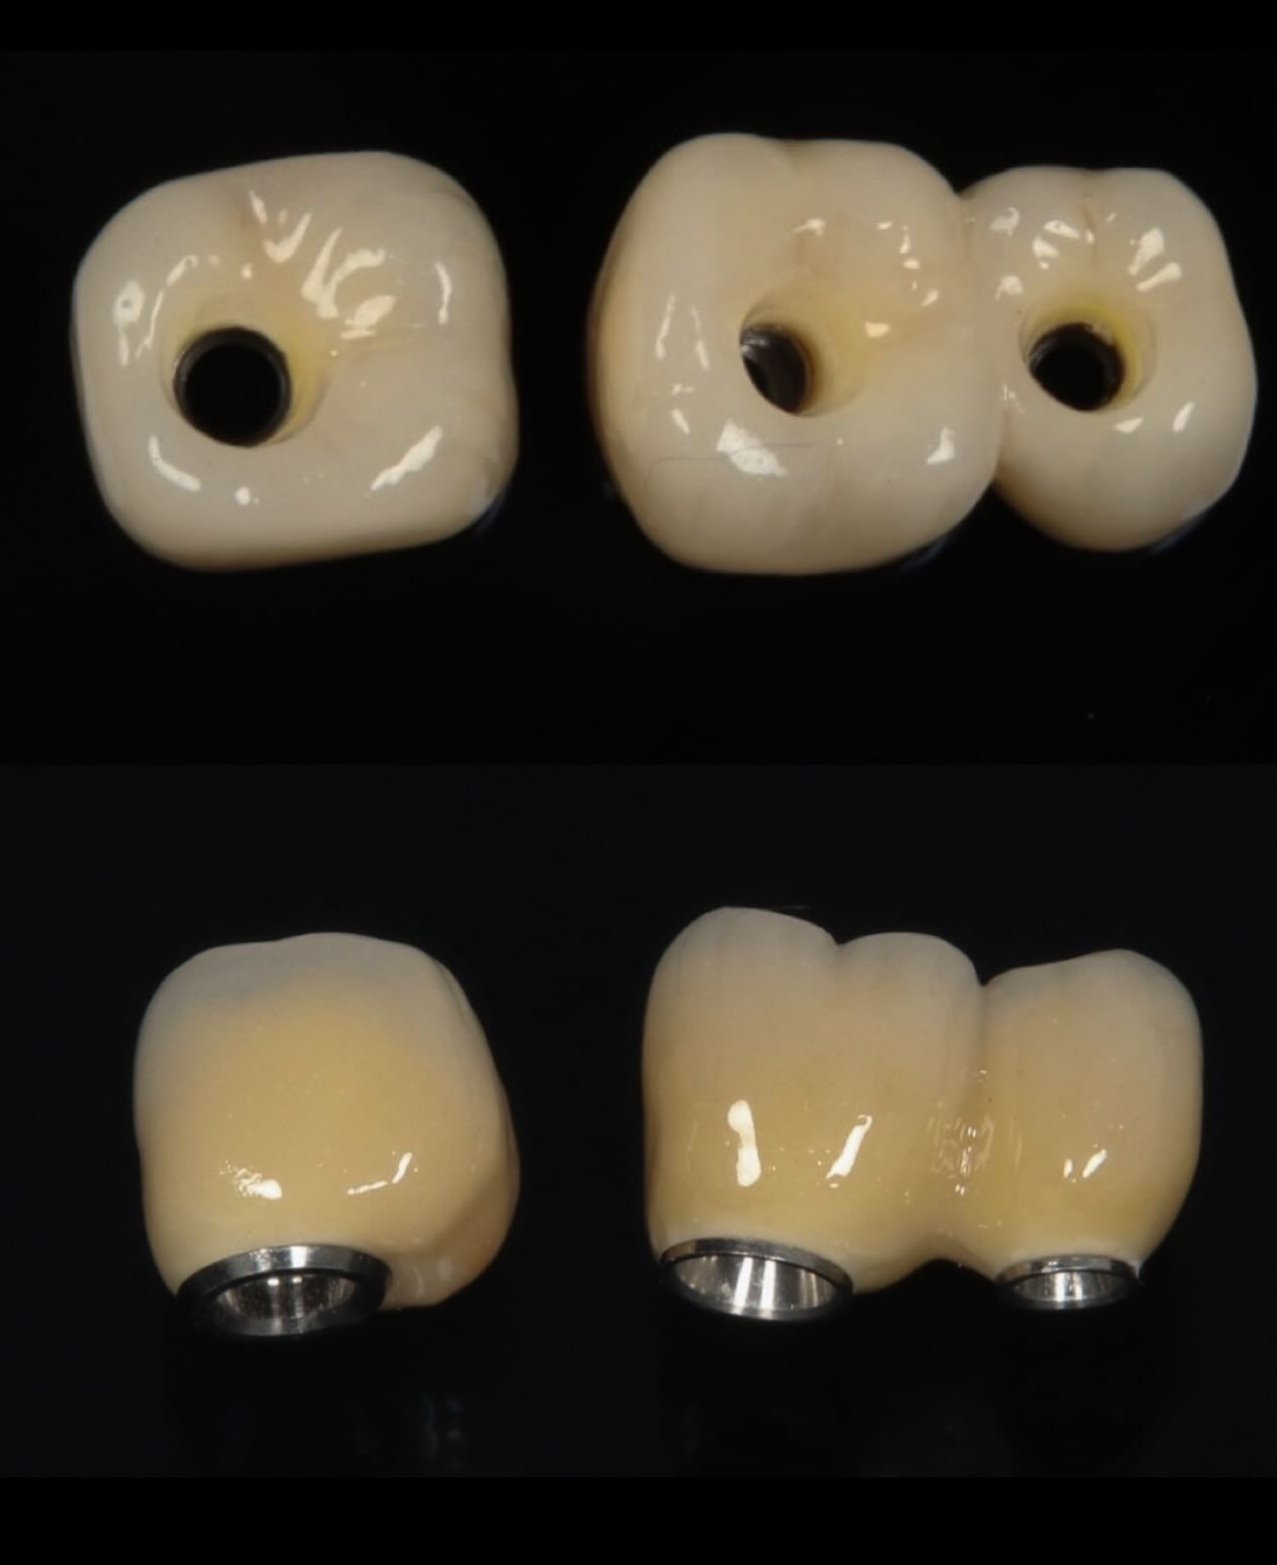

Galería de casos

Algunos resultados obtenidos en nuestra clínica.

Caso implantes 1 Caso implantes 2 Caso implantes 3 Caso implantes 4 Caso implantes 5 Caso implantes 6 Prótesis sobre implantes - Caso 7 Prótesis sobre implantes - Caso 8 Prótesis sobre implantes - Caso 9

4. Rehabilitación: instalación de corona, puente o prótesis fija.